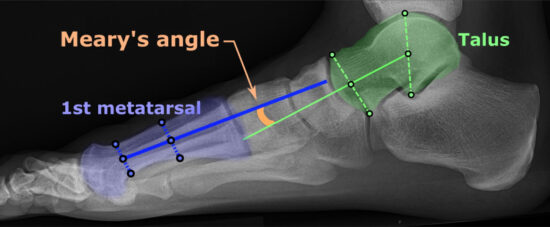

Included were 322 feet belonging to 177 children, with the mean age of 11.8 (SD = 2.2) years. The pain was perceived in 52% of the feet; of these, 74% in the medial arch. In the group with pain, 31 feet received a gait analysis following surgery. The radiological parameters, talus-1 and -2 metatarsal angles and the gait parameter, calcaneal lateral shift during walking showed a significant difference (P ≤ .004) between the no pain and pain groups and were associated (R2 ≥0.14, P ≤ .04) with the reduction in pain following surgery. The increased talus-1 and -2 metatarsal angles and the calcaneal lateral shift may cause increased tension on the soft-tissues along the medial side of the foot and may produce pain. Therapies aiming at improving the medial arch pain should be directed to normalize the talus-1 or -2 metatarsal angles and the calcaneal lateral shift.